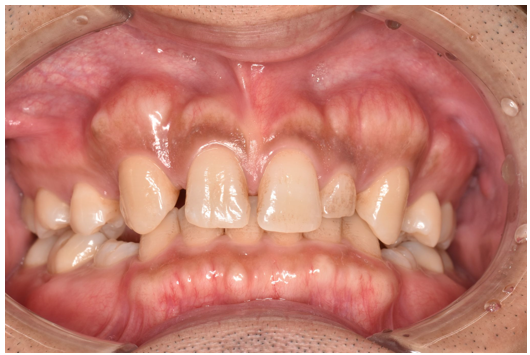

general 一般歯科

• 一般歯科

一般歯科